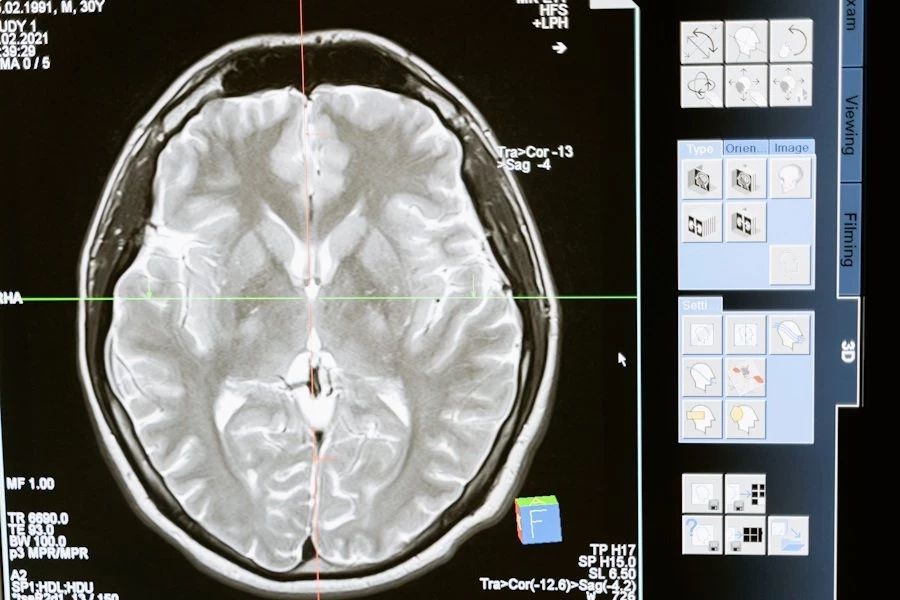

Фото из открытых источников

Ученые из University of Texas at Austin  разработали инновационные текучие чернила для электроэнцефалографии (ЭЭГ). Этот метод исследования активности мозга стал не только точнее, но и комфортнее для пациентов.